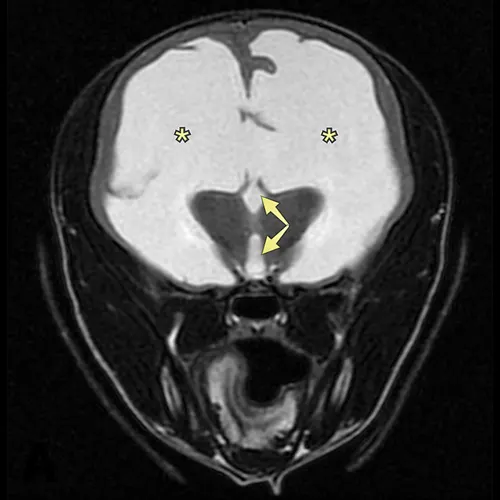

MRI image of brain showing large regions of hyperintensity.

FIGURE 4

Transverse MRI at the level of the thalamus demonstrating severe enlargement of the lateral ventricles (asterisks) and third ventricle (arrows)